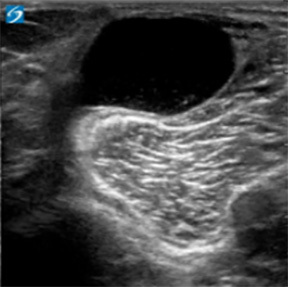

Knee Posterior Medial Knee Baker's Cyst Transverse Image